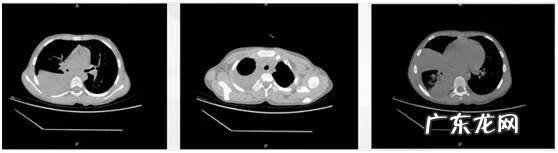

文章插图

胸部CT:右肺感染,右下肺为著,右侧胸腔液,左侧胸膜局部稍增厚